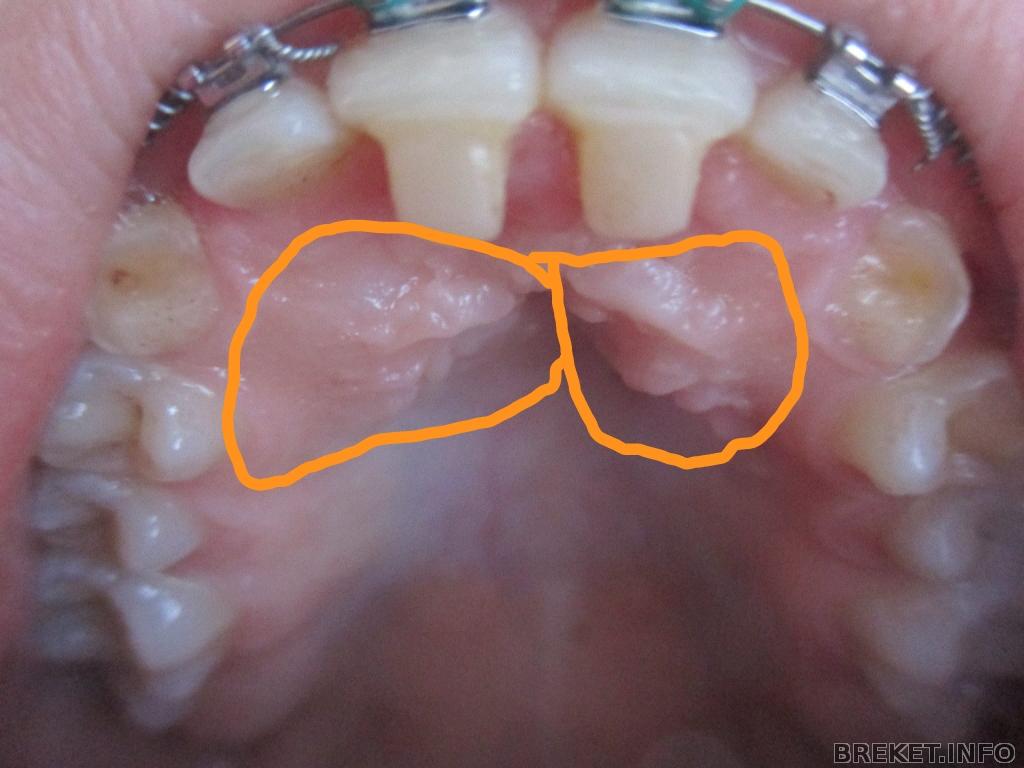

те самые ретинированные клыки которые не хотят вылазить .